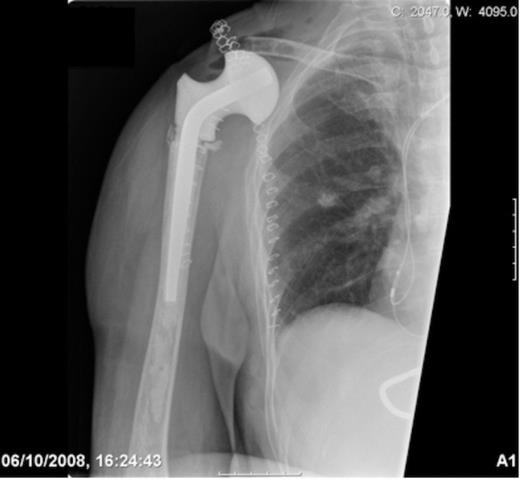

Post-operative radiograph demonstrating reconstruction using a hip spacer following extra-articular scapula resection

During the pre-operative consent process the patient stated if it was found that limb salvage was not technically possible intra-operatively, she did not wish to have a forequater amputation conducted and would rather the tumour be left untreated due to cosmetic concerns. A Tickhoff-Linberg procedure of the right shoulder was subsequently conducted with en-bloc resection of the scapula, distal clavicle and proximal humerus. In order to reconstruct the shoulder girdle, a hip spacer (spacer G by Orthodynamics) was cemented into the proximal humerus with the soft tissues tensioned appropriately. A synthetic mesh (LARS ligament by Corin) was then sutured over the prosthesis and secured to the osteotomised clavicular remnant and chest wall with non-absorbable sutures.

The patient made an uneventful post-operative recovery. The histopathological report confirmed a high-grade spindle cell sarcoma that had been completely excised with 2mm margins. Her wounds healed well with no complications and she retained very good hand, elbow and wrist function but no active motion of her shoulder.

Over three years following surgery she is alive and well, having been continuously disease free with no evidence of local or distant recurrence. Currently her Musculoskeletal Tumour Society Score (MSTS) score is 63 % and her Toronto Extremity Salvage Score (TESS) is 49% (7,8).